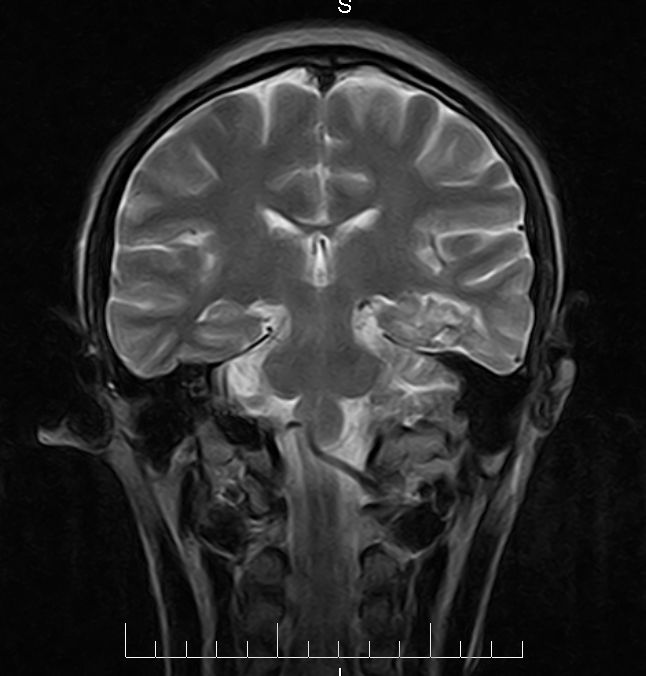

标题: MRI2379:30岁,男,癫痫10年,请各位看一下;CT示:左颞叶钙 [打印本页]

标题: MRI2379:30岁,男,癫痫10年,请各位看一下;CT示:左颞叶钙

左颞叶区见不规则点状混杂信号影

支持2楼 左颞叶区见不规则点状混杂信号影,考虑动静脉畸形。

考虑左侧颞叶脑血管畸形(avm)。----t1低等高混杂信号,t2等高信号周边较多流空血管影[冠状位明显],mra左侧大脑中动脉受压,远侧聚集.